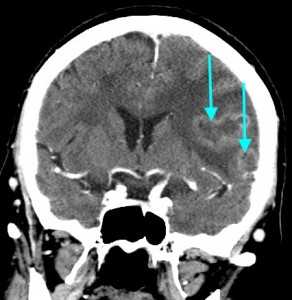

КТ-ПРИЗНАКИ МЕТАСТАЗОВ В ГОЛОВНОЙ МОЗГ

Как выглядят метастазы в головной мозг на компьютерной томографии (КТ)? Практически во всех случаях выявляется единичное (реже) либо множественные (чаще) объемные образования, которые отвечают следующим параметрам:

- Форма неправильная или сферическая

- Структура неоднородная, в центре очага может обнаруживаться область низкой плотности, обусловленная некрозом и распадом центральной части опухоли. По периферии — более плотный «ободок», который отражает активную часть опухоли, имеющую кровеносные сосуды и обладающую способностью к росту. Этот «ободок» окружен зоной низкой плотности, отражающей отек ткани мозга. Ширина данной зоны может быть различной — от нескольких мм до нескольких десятков см. Относительно однородная структура без наличия участка низкой плотности в центре и без перифокального отека. Такая структура метастаза свидетельствует о его относительной «доброкачественности»

- Отношение к прилежащим мозговым структурам. Очаги могут оказывать объемное воздействие различной степени выраженности на прилежащие отделы мозга, вызывая их смещение. Например, объемное образование в височной доле чаще всего приводит к выбуханию гиппокампа под намет мозжечка (височно-тенториальная дислокация), объемное образование мозжечка может воздействовать на мозговой ствол, приводя к его сдавлению, и т. д. Смерть при метастазах в мозг может наступить в результате сдавления мозгового ствола и нарушения дыхания и сердечной деятельности. В зависимости от локализации, вторичные очаги могут приводить к сдавлению церебральной ликворной системы, приводя к развитию окклюзионной гидроцефалии (резкому расширению центральных ликворных пространств на фоне повышения внутримозгового давления при окклюзии путей оттока ликвора из полости черепа)

- Тип роста. Метастазы могут обладать инфильтративным типом роста (расти, разрушая окружающие ткани) и экспансивным типом (расти, раздвигая окружающие ткани). В первом случае они чаще всего дают осложнения в виде кровоизлияния, то во втором обычно обуславливают возникновение дислокаций.

- Параметры контрастного усиления. Типичные вторичные опухоли в головном мозге увеличивают свою плотность в периферических отделах при внутривенном введении контраста, принимая вид «кольца», «полукольца», «спирали». Гораздо реже наблюдается равномерное контрастное усиление очага. Обычно центральная зона опухоли не усиливается, как и область перифокального отека.

Метастазы головного мозга, фото. На КТ с контрастным усилением у пожилой пациентки (в верхнем ряду слева) с жалобами на головные боли выявлены множественные объемные образования в левом полушарии мозга, интенсивно накапливающие контрастное вещество. Образования имеют характерную форму в виде «кольца». На изображениях в нижнем ряду и вверху справа определяются множественные очаги в головном мозге: отчетливо видны округлые образования с более плотным «ободком» по периферии, располагающиеся в левой теменной доле.